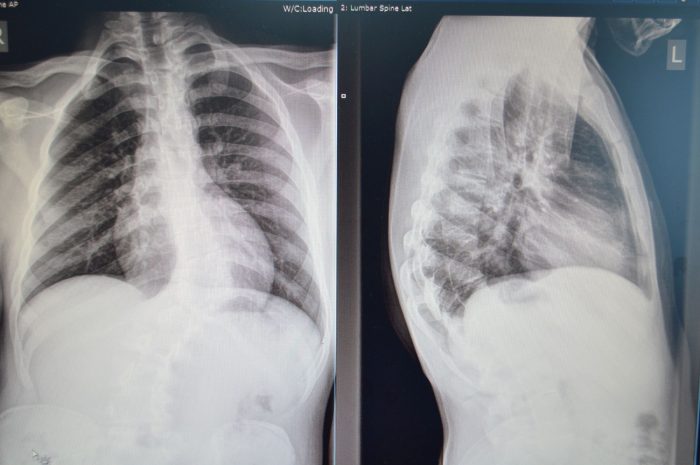

U UKC Tuzla urađen složen operativni zahvat skolioze kičme

Operativni tim Klinike za ortopediju i traumatologiju Univerzitetskog kliničkog centra Tuzla uradio je složen operativni zahvat prilikom kojeg je odstranjen pogrešno razvijen pršljen i izvršena korekcija deformiteta kičme. Prema riječima v. d. načelnika Klinike za ortopediju i traumatologiju UKC Tuzla, doc. dr. Aleksandra Vujadinovića, kod šesnaestogodišnjeg pacijenta iz Konjica urađena je ekscizija hemivertebrae prilikom koje…